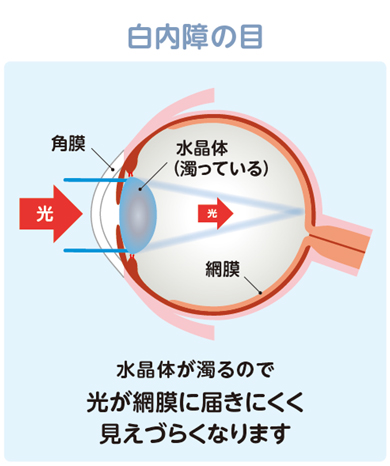

白内障について

目の中の水晶体が濁り、光が通りづらくなりみえづらくなる状態です。